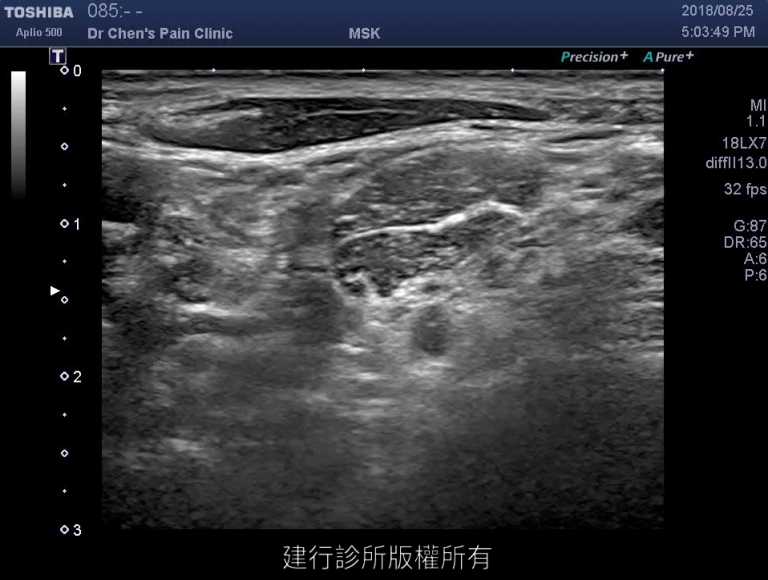

超音波治療實作錄影:第四頸椎

治療時,可以根據患者的症狀與影像結果,在超音波的導引下